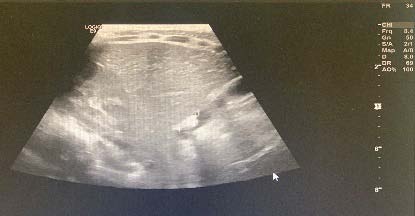

? Dedifferentiated liposarcoma ? Myxoid liposarcoma ? Pleomorphic liposarcoma ? Myxoid pleomorphic liposarcomaIn atypical lipomatous tumour/well differentiated liposarcoma adipocytic variant consists out of cells that vary substantially in size as well as cells that have Dedifferentiated liposarcoma can arise as a synchronous lesion in 90% of cases and as metachronous lesion in 10% of cases 6 . These tumours exhibit a wide morphological spectrum and histologically show areas of high grade, poorly differentiated sarcoma resembling high-grade myxofibrosarcoma, fibrosarcoma, malignant solitary fibrous tumour or pleomorphic sarcoma not otherwise specified. Dedifferentiated liposarcomas can be of variable histological grade 5 . Dedifferentiated liposarcomas is an aggressive disease, arising most commonly in the retroperitoneum and is associated with high rates of local and metastatic recurrence and disease specific mortality 7 Use of the term atypical lipomatous tumour is determined by tumour location and resectability. In locations such as the retroperitoneum, it is usually impossible to obtain a wide tumour free surgical margin of more than 2cm, thus local recurrence is common and leads to mortality, seen in the absence of dedifferentiation or metastases The introduction of computed tomography (CT), magnetic resonance imaging (MRI), and ultrasonography have greatly enhanced our capability to make the diagnosis of abdominopelvic neoplasms and determine and direct treatment, as well as observe the progress of the neoplasm and effect of treatment over time. Identification of a retroperitoneal mass at imaging is a challenging task for radiologists, however the presence of fat within a retroperitoneal lesion is helpful in refining the differential diagnosis 9 ? On ultrasound appearance it is hyperechoic and may demonstrate posterior acoustic shadowing . It is easy to recognize fat within a lesion due to its characteristic imaging appearance: